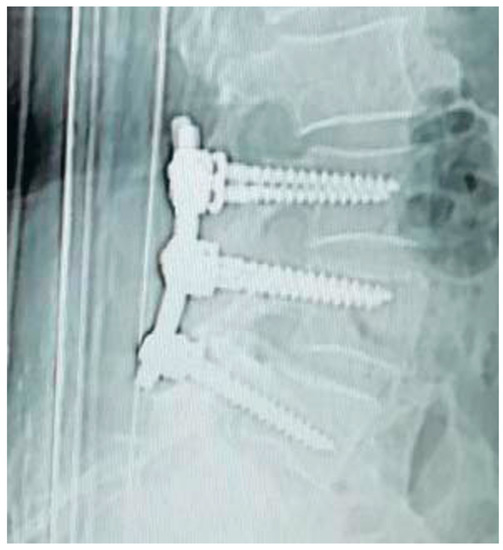

Figure 6, Figure 7, Figure 8 and Figure 9 show examples of pre- and post-operative X-ray shots.

Figure 6. Post-operative sagittal X-ray check—patient code: 2ATL3L4L5110.

Figure 8. Post-operative sagittal X-ray check—patient code: 5BML4L501.